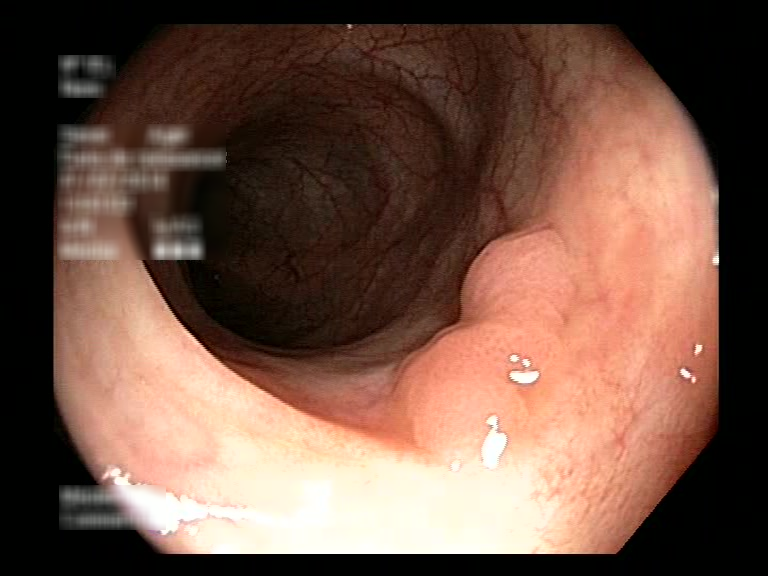

| Lesion | White Light Frame | NBI Frame | White Light Video | NBI Video | Camera Calibration |

| hyperplasic_01 |  |

|

WL.mp4 | NBI.mp4 | cam.xml |